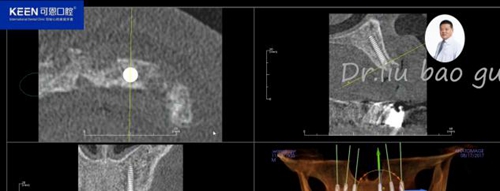

手術(shù)前種植軟件設(shè)計(jì)方案